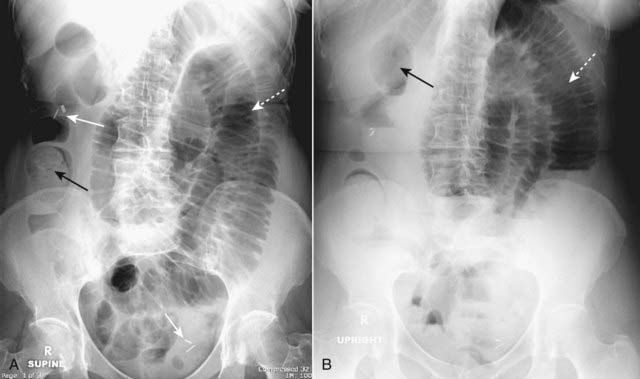

Figure 14-6 Partial small bowel obstruction, supine (A) and upright (B).

A partial or incomplete mechanical small bowel obstruction allows some gas to pass the point of obstruction, possibly on an intermittent basis. This can lead to a confusing picture because gas may pass into the colon (solid black arrows) and be visible long after the large bowel would be expected to be devoid of gas. The important observation is that the small bowel is disproportionately dilated (dotted white arrows) compared to the large bowel, a finding suggestive of small bowel obstruction. Partial or incomplete small bowel obstructions occur more often in patients in whom adhesions are the etiology. Notice the clips (solid white arrows) attesting to prior surgery.